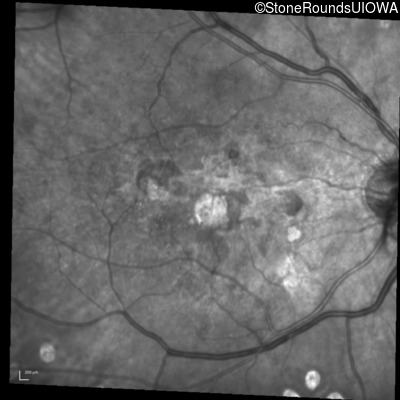

Infrared Fundus Photograph - Right - 20/150

Exemplar